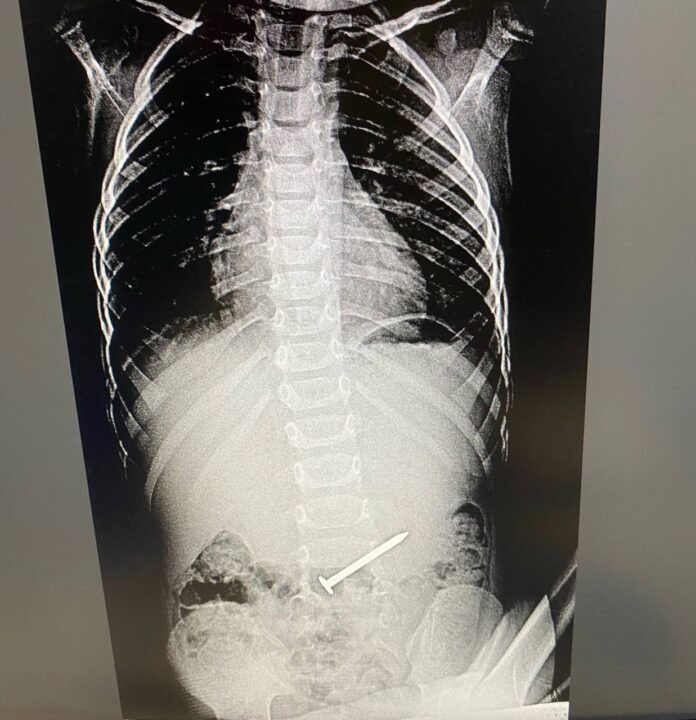

В альметьевскую Детскую городскую больницу попал трехлетний малыш. Выяснилось, что ребенок проглотил гвоздь. Произошло это во время игры. Позже мальчик все рассказал маме. Отмечается, что посторонний предмет в животе его совсем не беспокоил.

Маленького пациента экстренно госпитализировали. При проведении ФГДС выяснилось, что гвоздь длиной в пять-шесть см находился в двенадцатиперстной кишке. Ситуация осложнилась тем, что инородный предмет встал поперек. Гвоздь мог повредить стенки кишки. Как сообщает пресс-служба Детской городской больницы, медикам удалось «стащить» инородное тело в желудок, что технически было тяжело. А уже после гвоздь извлекли корзинкой Дормиа.

Маленького пациента экстренно госпитализировали. При проведении ФГДС выяснилось, что гвоздь длиной в пять-шесть см находился в двенадцатиперстной кишке. Ситуация осложнилась тем, что инородный предмет встал поперек. Гвоздь мог повредить стенки кишки.

Как сообщает пресс-служба Детской городской больницы, медикам удалось «стащить» инородное тело в желудок, что технически было тяжело. А уже после гвоздь извлекли корзинкой Дормиа.